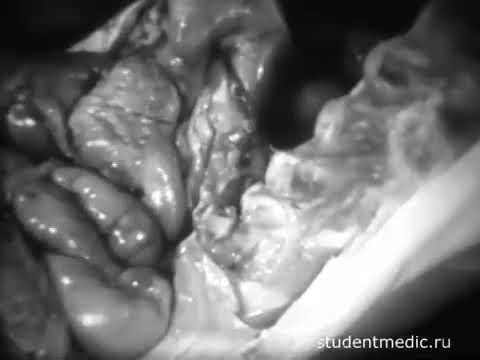

вскрытие трупа по Шору(16+) учебный фильм для медвузов 1978